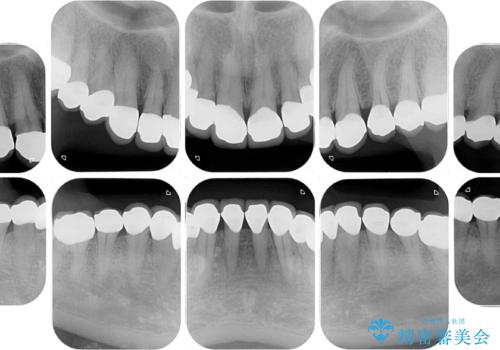

- 前歯の変色や欠損による隙間を気にして来院された患者様です。

上顎前歯は樹脂による変色を覆い隠す処置が行われていましたが、汚れが溜まりやすく厚みも増している状態でした。

上顎前歯は樹脂を外し、下顎前歯の隙間はそれぞれの歯を大きくするように補綴治療を行うことで隙間を埋めることとしました。